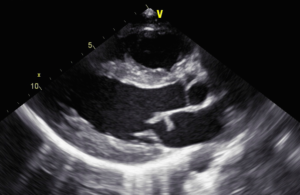

- Trans-esophageal echo [Fig 2,3] showed a mobile mass on the mitral valve. EF was 66% with normal LV function.